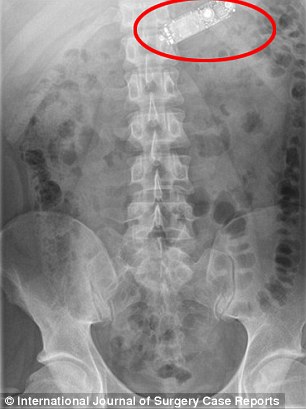

وأظهرت الأشعة السينية جهاز الهاتف وهو موجود في معدة الشاب، وحاول الأطباء اقتلاعه بالمنظار عن طريق المريء، وبعد فشل المحاولة أجبروا على إخضاعه لعملية جراحية عاجلة وشق بطنه لاستخراج الهاتف قبل أن يمزق معدته، وفقاً لصحيفة دايلي ميل البريطانية.